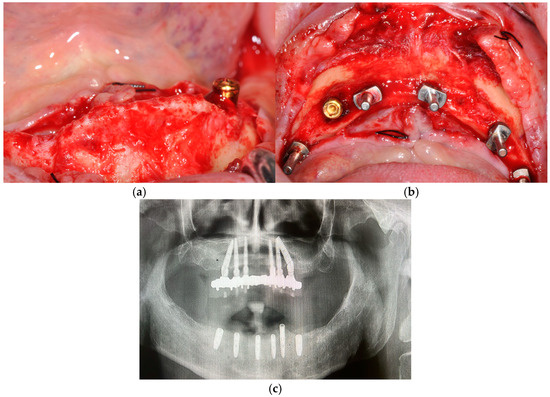

The Effectiveness and Predictability of BioHPP (Biocompatible High-Performance Polymer) Superstructures in Toronto-Branemark Implant-Prosthetic Rehabilitations: A Case Report

3. Case Presentation